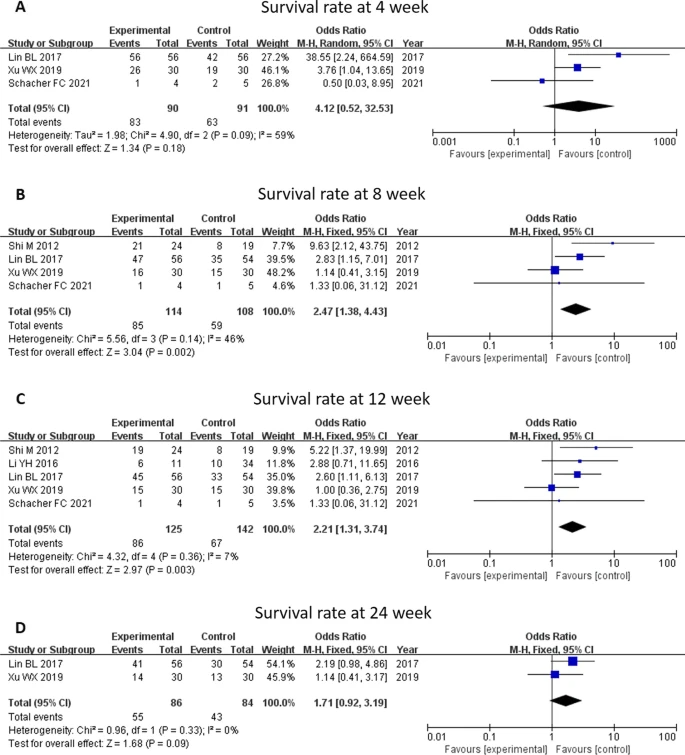

近期,武漢大學人民醫院江應安教授、解放軍總醫院第五醫學中心石磊教授等研究者合作,對13項間充質干細胞治療肝硬化、慢性肝衰竭急性發作(ACLF)的臨床研究進行了薈萃分析。

結果表明,間充質干細胞的治療安全,并且可以改善終末期肝病患者的肝功能和生存率。

這項薈萃分析對過去10年內的13項臨床研究進行了綜合評估,涉及854名患者。這些研究主要關注了MSC治療對肝功能的影響,同時評估了骨髓和臍帶來源的MSC對逆轉肝硬化或拯救急慢性肝衰竭患者的效果。

研究結果顯示,間充質干細胞治療能夠顯著改善患者的肝功能參數,如MELD評分、TB水平和ALB水平。與常規治療相比,這意味著間充質干細胞治療可以有效地恢復肝臟的正常功能,從而提高患者的生活質量。

此外,間充質干細胞治療還能顯著提高肝硬化和ACLF患者的生存率。這一發現對于那些無法接受肝移植或其他傳統治療的患者來說,無疑帶來了新的希望。

更進一步的亞組分析顯示,相比肝硬化患者,ACLF患者在多數時間點上從MSC治療中受益更多。本研究表明間充質干細胞治療可能為ACLF的治療提供另一種潛在的選擇。

值得注意的是,這些研究中并沒有報告間充質干細胞治療引發的任何嚴重副作用或不良事件。這進一步證實了MSC治療的安全性,使其成為一個可靠的治療選擇。